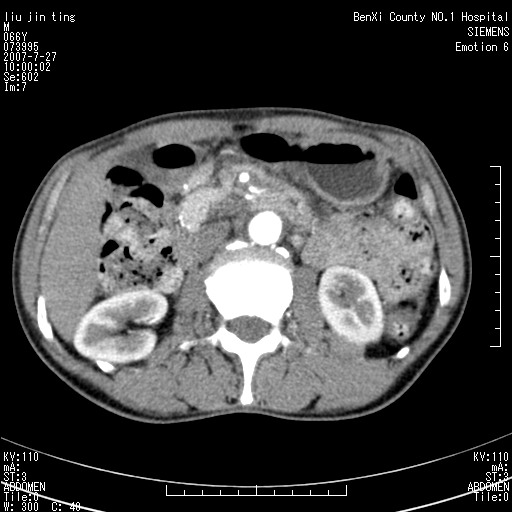

沿着肠系膜上动脉呈匍匐性生长的软组织肿块,形态不规则,包绕肠系膜上动脉,呈明显强化,考虑来源于肠系膜的恶性肿瘤

肠系膜根部肿块,累及肠系膜上动脉,考虑肿大淋巴结累及肠系膜上动脉.

腹腔干至肠系膜上动脉水平肿大淋巴结影可能性大.

沿着肠系膜上动脉呈匍匐性生长的软组织肿块,形态不规则,包绕肠系膜上动脉,呈轻-中度强化,考虑来源于肠系膜的恶性肿瘤。

钩突是正常的,只见腹膜后淋巴结的肿大,考虑淋巴瘤或转移可能。

支持!恶性纤维组织细胞瘤可能,与淋巴瘤及淋巴结转移鉴别(腹主动脉周围清晰,其他部位亦未见明显肿大淋巴结)。